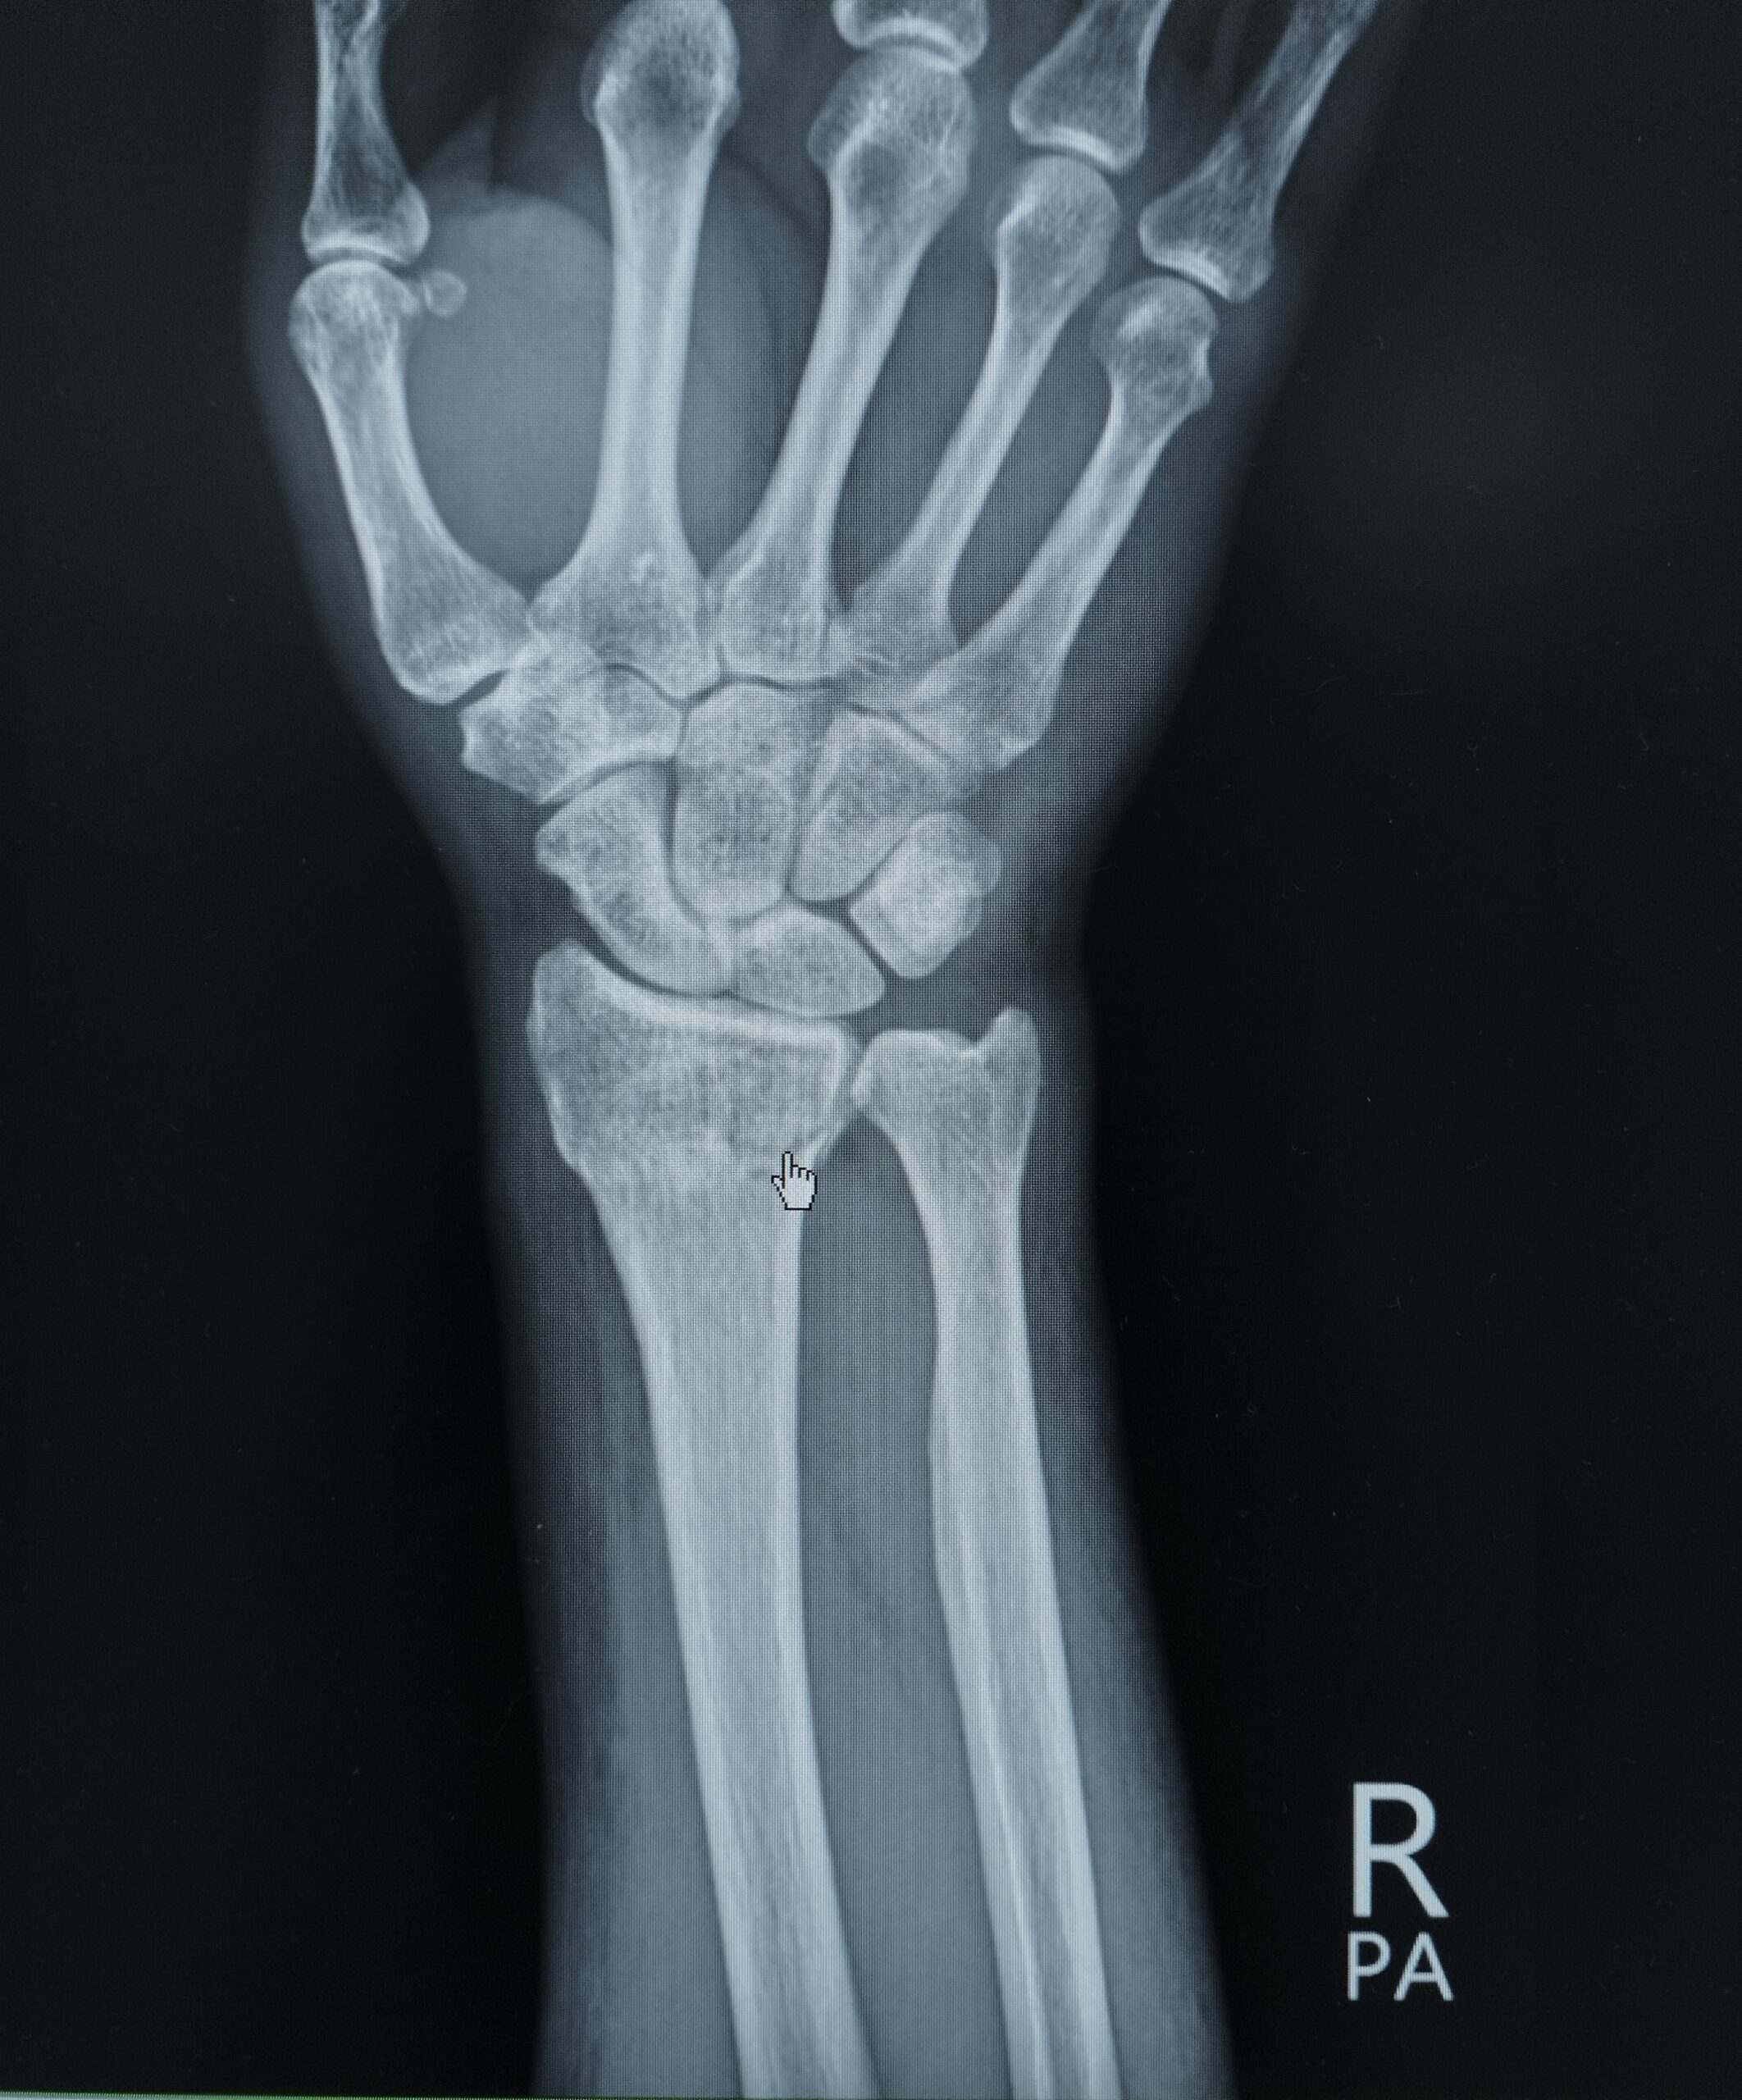

The Oblique View of the Wrist is a specialized X-ray projection used to provide an angled image of the carpal bones, particularly helpful for evaluating the trapezium, scaphoid, and the articulations between the carpal bones and metacarpals. In this view, the patient’s forearm is placed on the image receptor with the wrist rotated externally about 45°, so the hand rests on its medial (ulnar) border. The X-ray beam is directed anteroposteriorly, centered at the midcarpal region. This view helps in detecting subtle fractures, especially of the scaphoid and trapezium, and in assessing joint spaces, alignment, and soft tissue swelling that may not be clearly visible in standard PA or lateral views.

Oblique view